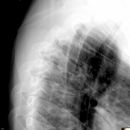

Foramen arcuale bzw Kimmerle Anomalie